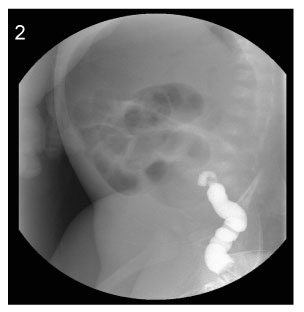

Fig. 2

Image of barium enema at the age of 8days (Case No. 3).

The contrast cannot advance further.

Fig. 2 Image of barium enema at the age of 8days (Case No. 3). The contrast cannot advance further.